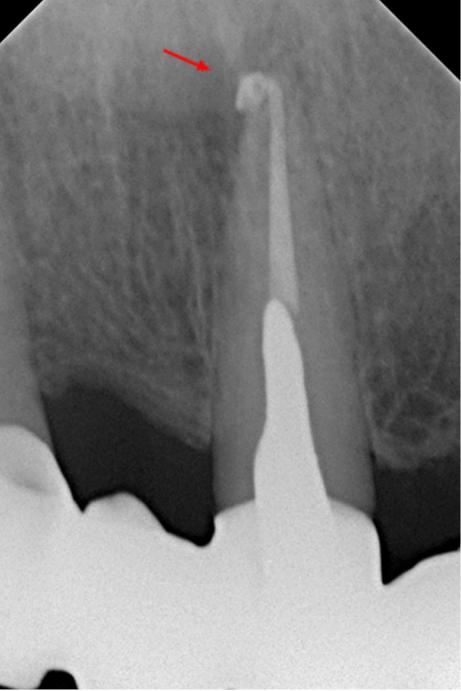

В связи с наличием у пациента жалоб и клинических симптомов принято решение о проведении ревизии корневого канала 21 зуба. Проведена терапия с помощью гидроокиси кальция в течении 4-х недель (снимок 3). Пломбировка канала гуттаперчей и корневым герметиком.

На контрольном снимке через 12 месяцев после лечения отмечается репарация тканей в области верхушки 21 зуба (снимок 4). Жалобы отсутствуют.